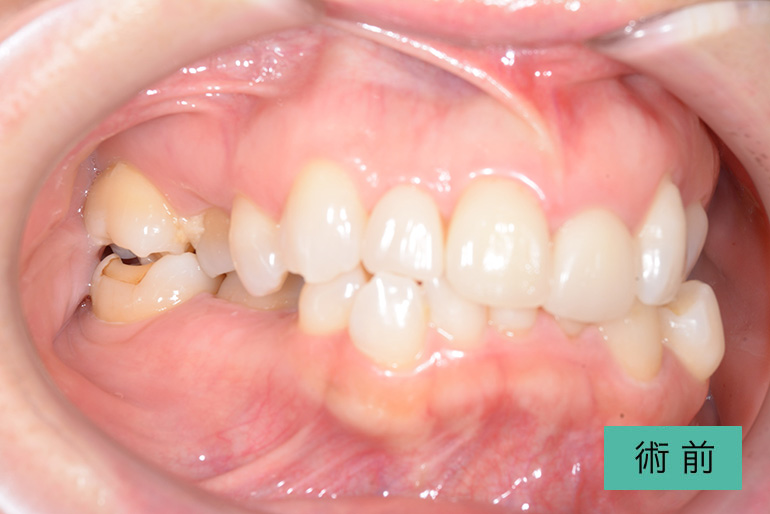

オールセラミック①

| 治療内容 | 上顎インビザライン矯正 右上1番から左上の2番のセラミック冠 上顎前歯の叢生、右上犬歯の捻転の改善のため、上顎のみインビザライン矯正を行なった また、根尖病巣があった為補綴を除去、顕微鏡根管治療を行い、セラミック冠を装着した |

| 治療期間・回数 | 約8ヶ月、15回(インビザライン矯正) 約4ヶ月、6回(補綴治療) |

| 費用(税込) | ¥275,000 (上顎インビザライン矯正) ¥495,000(165,000/1本)(補綴費用) ※自由診療 |

| リスク・副作用 | 疼痛、補綴物の脱落、咬合違和感、破折 |